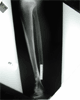

Post

Op

Stabilised using ligamentotaxis,fibular fixation and ring fixator application